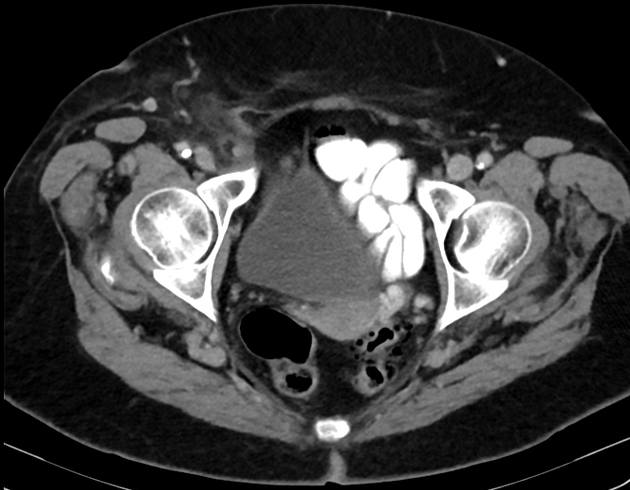

Thoát vị De Garengeot

» Thông tin: Nữ giới – 85 tuổi.

» Lâm sàng: Đau háng phải.